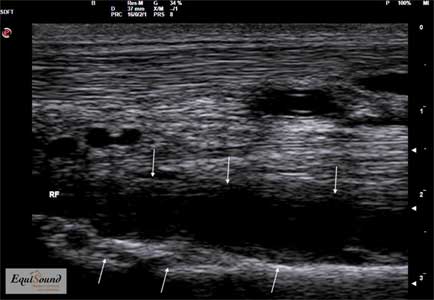

Longitudinaal echografisch beeld van de proximale aanhechting van de interosseus bij een paard met een degeneratieve blessure ter hoogte van de mediale lob. (Links is proximaal, rechts is distaal)

Transversaal echografisch beeld van de proximale aanhechting van de interosseus bij een paard met een degeneratieve blessure ter hoogte van de mediale lob. (Links is lateraal, rechts is mediaal)